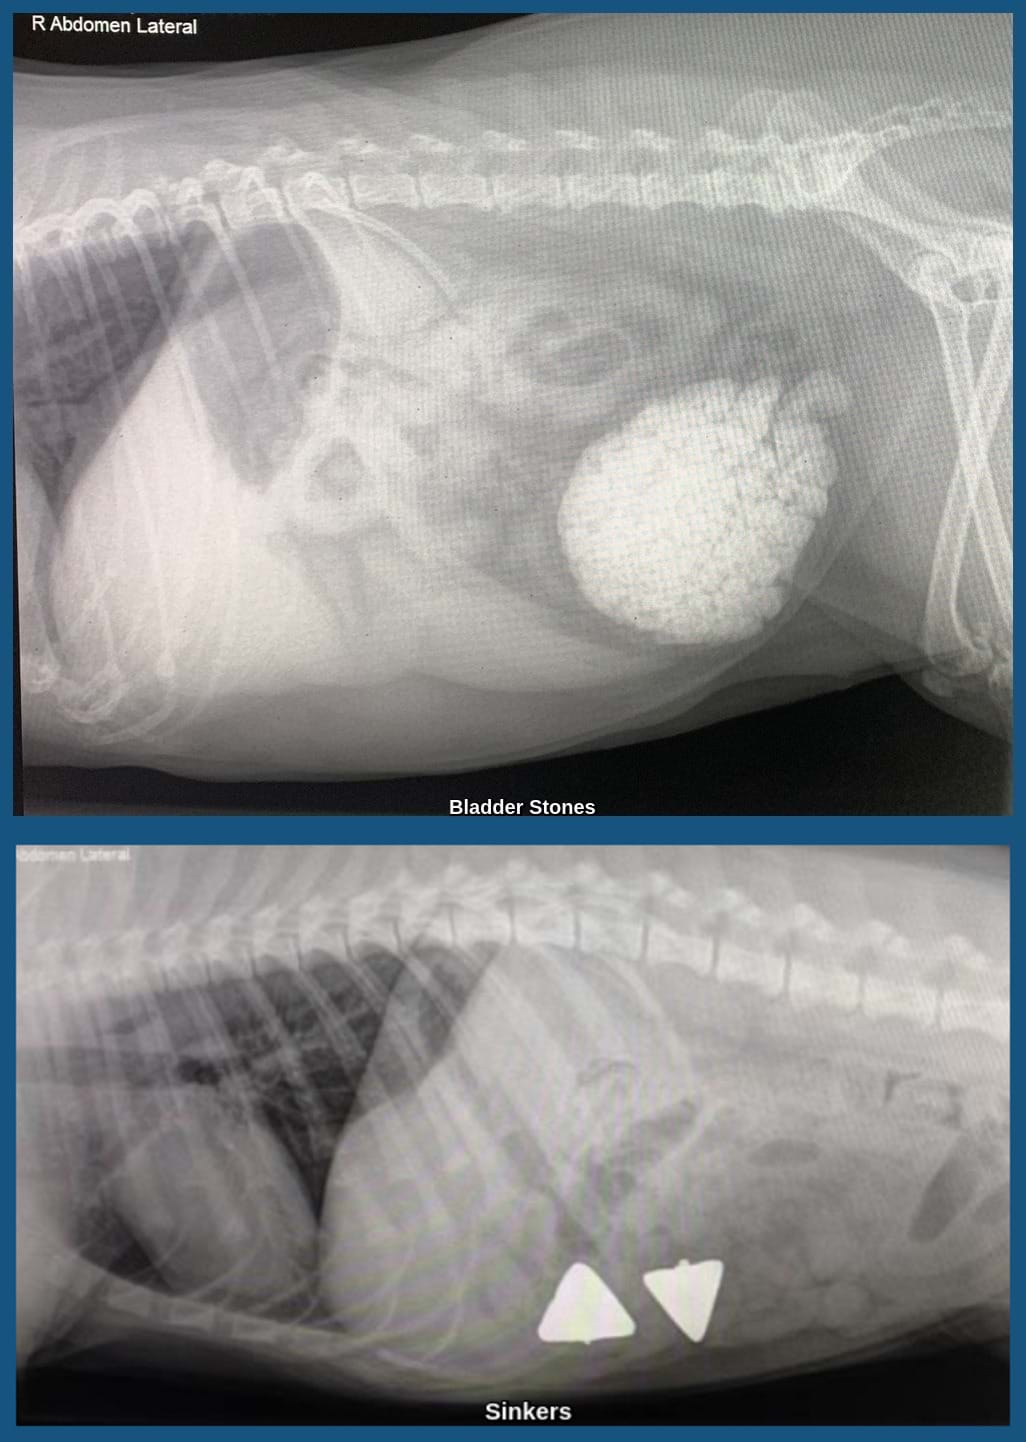

We offer onsite X-ray services to assist with diagnoses and treatment plans, using the most up-to-date equipment. We have a digital X-ray system that allows us to access specialist help for more complex cases.